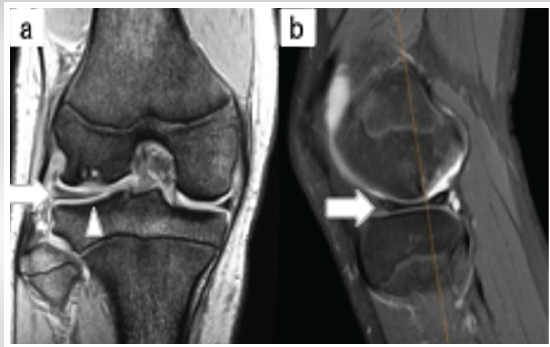

MRI revealed a lateral discoid meniscus (Mink classification grade 2), with the meniscus absent at the site of OCD. The anterior and posterior cruciate ligaments were intact (Fig. 3).

Figure 3: (a) Magnetic resonance image (T2* coronal section) showing a lateral discoid meniscus (Mink classification grade 2) (white arrowheads). (b) Magnetic resonance image (fat-suppressed T2-weighted sagittal section) showing the absence of the meniscus at the site of osteochondritis dissecans (white arrowhead).